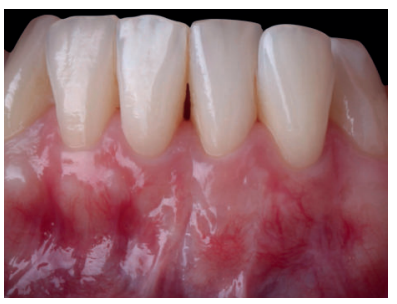

El examen clínico periodontal reveló la presencia de recesión gingival de 5 mm en el diente 31 con una profundidad de sondaje vestibular de 2 mm (perdida de inserción clínica de 7 mm). Presentaba inflamación gingival, además de un frenillo labial inferior insertado en el margen apical de la recesión gingival. El tejido queratinizado faltaba por completo a nivel del diente con recesión (Figura 1). Debido a que el defecto gingival se extendía más allá de la línea mucogingival, así como a la presencia de malposición dentaria, la recesión se categorizó como clase III de Miller6 y RT2 de Cairo7 .

Previamente a la intervención, la paciente se enjuagó durante 1 minuto con un colutorio de clorhexidina. La técnica quirúrgica comenzó con la preparación del lecho receptor, para ello se realizó una incisión sulcular a espesor parcial a nivel de la recesión, se continúo diseccionando apical y lateralmente, extendiéndose de 3 a 5 mm de la recesión para permitir la entrada del ITC y su estabilización. Posteriormente, se realizó una incisión en el fondo de vestíbulo, dejando un puente de tejido que servirá para un doble aporte sanguíneo al injerto (Figura 2).